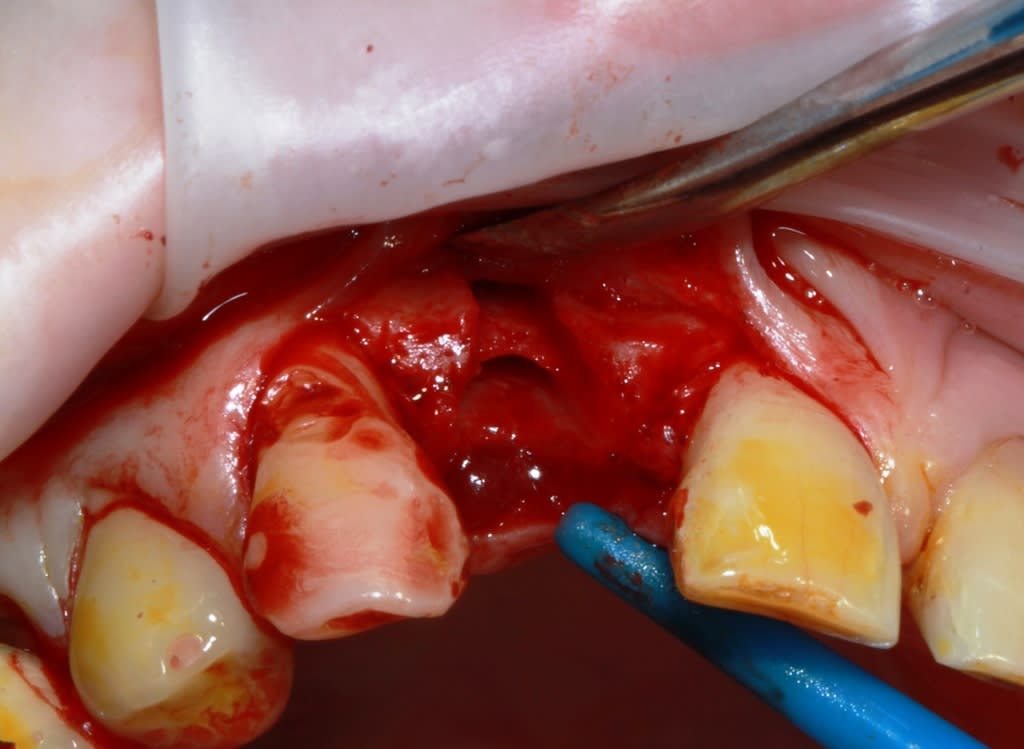

un petit cas comme j'aime, perte de 11, avec atteinte de la paroi vestibulaire.

Manipulation de la paroi palatine, afin de déplacer la moitié de l'os en vestibulaire, et pose d'un Px (Anthogyr) utilisation, de lame 11, ostéotome demi lune de Tatum, spreader (Meissinger) et divers.

afin d'éviter la "casse", il faut un os assez souple et prendre son temps.

Le volet n'est pas vraiment "déplacé", il reste solidaire en apical, il est donc "manipulé".

Il est important bien sûr qu'il n'y ai pas de pression dessus ensuite, donc provisoire collé ou rien.